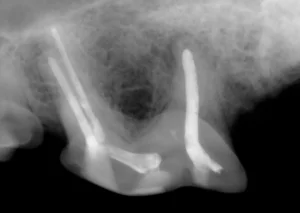

This is an x-ray of an upper 4th premolar that received root canal therapy. The filling material in all three roots appears white in the image.

Essentially, root canal therapy allows salvage of the tooth by removing the affected inner pulp in a sterile manner. The pulp canal is then cleansed and filled in with dental materials. A final hard layer of composite (the white material that is often used for fillings in your own mouth) is placed on the tooth to provide a hard, protective outer layer. After the procedure, the tooth can once again be used for chewing and picking up items.